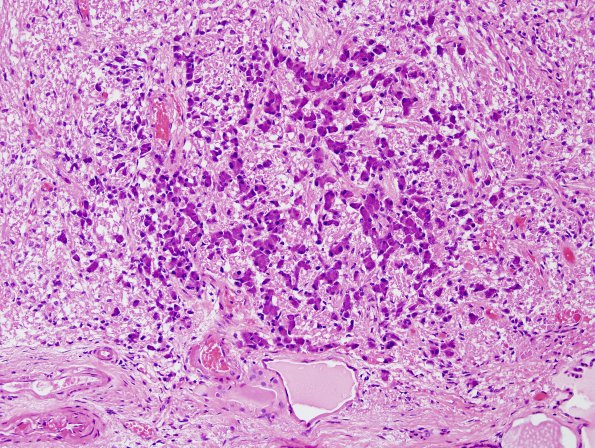

Another photogenic example of basophil invasion in the presence of intermediate lobe cysts. (H&E)